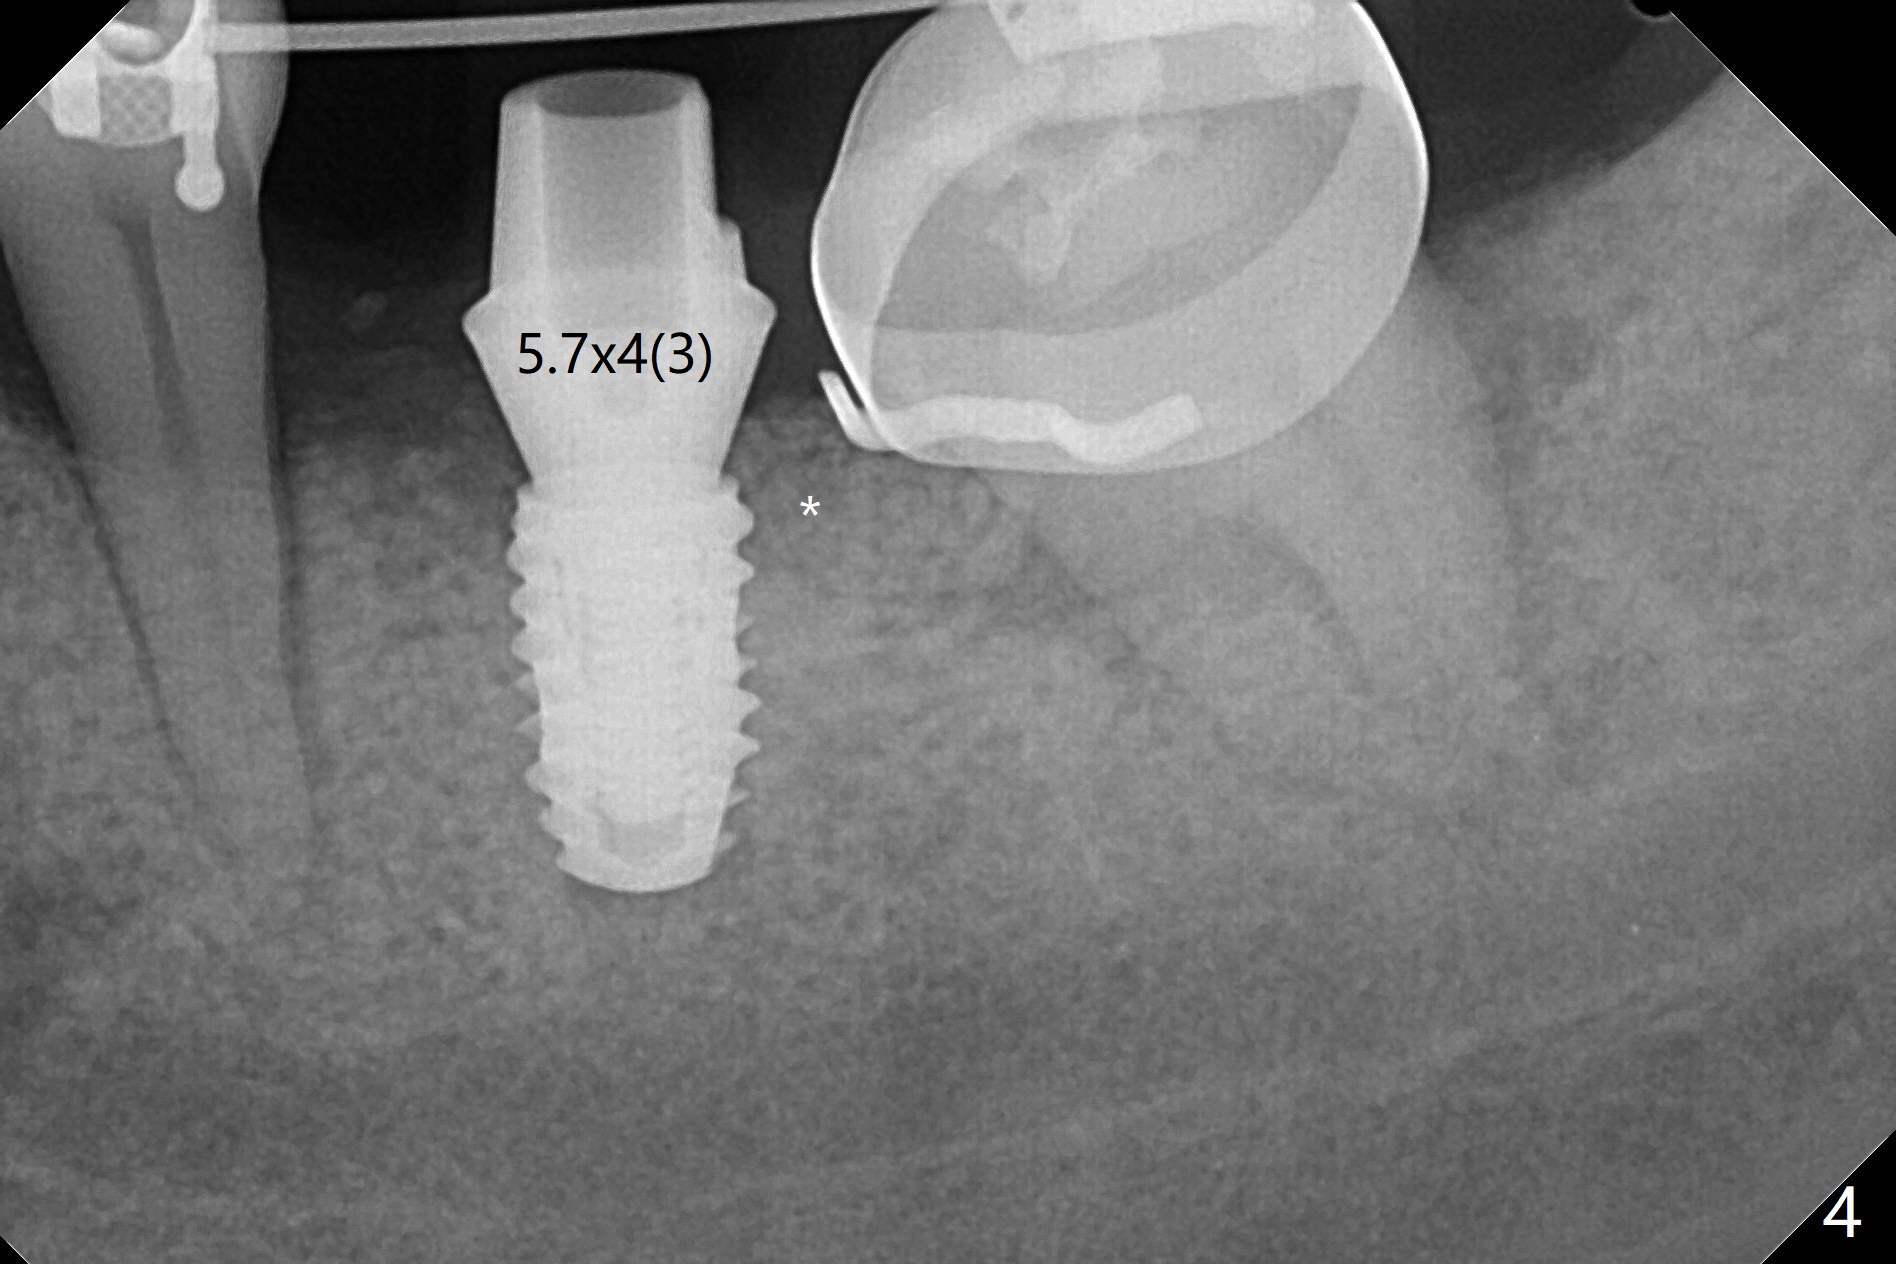

31岁女19号牙残根拔除,没有植骨,牙齿矫正创造了大约近远中10.5毫米空间,先锋钻深度8毫米(图一),远中舌侧骨质缺损(*)。使用4x7.3毫米钻头(实际长度8.5毫米)后,植入4.5x7.3毫米植体,远中大约3个螺纹暴露(图二)。使用4x8.5毫米钻头后,植体种深些(图三),但是根尖仍有空间(*)。再种深后(只有一个螺纹暴露),放置基台和粘性骨粉(图四:*),覆盖PRF,缝合,放置矫正钢丝和牙周敷料。